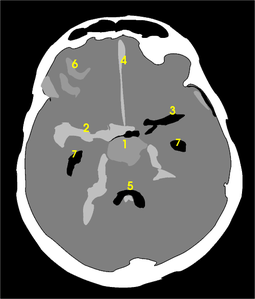

| CT scan of the brain showing subarachnoid hemorrhage as a white area in the center | |

نزف تحت العنكبوتية Subarachnoid hemorrhage (SAH)، أو subarachnoid haemorrhage، هو نزيف داخل الحيز تحت العنكبوتية subarachnoid space المحيط بالمخ، وهي المنطقة بين الغشاء العنكبوني arachnoid membrane والأم الحنون pia mater. فيه يحدث النزف ضمن الطبقة السحائية العنكبوتية. وأكثر الأسباب شيوعاً هو رضوض الدماغ، أما حالات النزف غير الرَّضِّيّ فتنتج عادة من انفجار أم دم aneurysm (وهي توسع كيسي غير طبيعي في شريان أو أكثر). ومن الأسباب الأخرى التشوهات الشريانية الوريدية، والتهاب الأوعية، وتسلخ الشرايين، واعتلالات التخثر، وخثار الجيوب الوريدية، وفقر الدم المنجلي، وتمزق شريان سطحي صغير. ويبقى السبب مجهولاً في نحو 14ـ22% من الحالات. وفيما يأتي نبذة عن النزف تحت العنكبوتية الناتج من أمهات الدم لكونه الأهم بينها.[1]

يعتمد بصفة رئيسة على تصوير الدماغ، ومن أكثر طرق التصوير استعمالاً التصوير الطبقي المحوري (الشكل3)، وبدرجة أقل المرنان المغنطيسي. وجدير بالذكر أن تصوير الدماغ قد يخفق في إظهار النزف في نحو 5% من المرضى، وفي هذه الحالة يمكن اللجوء إلى استقصاء آخر هو البزل القطني للسائل الدماغي الشوكي. وتظهر دراسة السائل وجود أعداد كبيرة من الكريات الحمر، مما يثبت حدوث النزف.

The Fisher Grade classifies the appearance of subarachnoid hemorrhage on CT scan:[4]

- Grade 1: No hemorrhage evident

- Grade 2: Subarachnoid hemorrhage less than 1 mm thick

- Grade 3: Subarachnoid hemorrhage more than 1 mm thick

- Grade 4: Subarachnoid hemorrhage of any thickness with intra-ventricular hemorrhage (IVH) or parenchymal extension